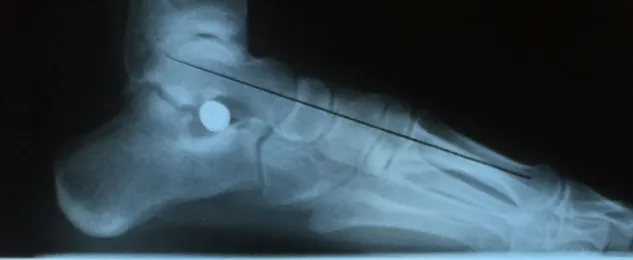

Pre and Postop Subtalar Implant and Percutaneous Achilles Lengthening Below. The first pics show wedging of the distal tibia physis causing ankle valgus due to constant pressure caused by the severity of the flatfoot (JT)